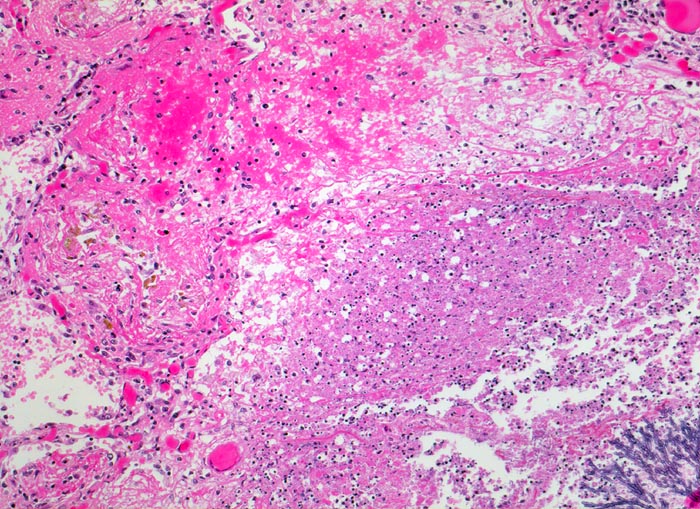

PathoPic – image database / PathoPic ID 4825 - Aspergilluspneumonie

Aspergilluspneumonie

Lunge

Randbereich eines Infiltratherdes. Angrenzend an die Pilzkolonie folgt ein Saum von zerfallenden neutrophilen Granulozyten und weiter aussen vitales Lungenparenchym mit hyperämischen Kapillaren und intraalveolären fädigen Fibrinexsudaten mit Einschluss von hämosiderinbeladenen Makrophagen.

Seit 14 Monaten bekannte chronische lymphatische Leukämie behandelt mit Chemotherapie. Der Patient entwickelt unter Therapie eine Pneumonie und verstirbt an einer Pilzsepsis.